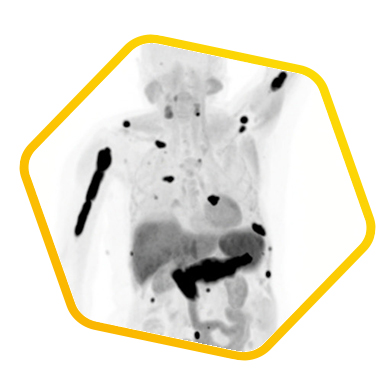

Theranostics is a revolutionary concept which brings diagnosis and therapy closer together than ever before. The biological distribution of a specific tracer can be observed from the diagnostic scan and later in the treatment phase, that type of tracer is used as a carrier of a treatment radiation dose targeted accurately to the tumor. As a result, the diagnostic scan serves as a simulation to forecast the possible treatment outcome, i.e., what we see is what we treat. Moreover, the carrier can even deliver the radiation dose to very small size lesion that we cannot see.

Through quantification of absorbed dose from post treatment scan, the treatment effectiveness can be reviewed in a comprehensive way. Examples are Fluorine-18/Lutetium-177 PSMA cancer treatment, Gallium-68/Lutetium-177 DOTA Conjugated peptides and Technetium-99m MAA/Yttrium-90 microspheres liver cancer treatment. Please click here for Radionuclide Therapy.